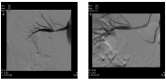

Background Fibromuscolar dysplasia (FMD) is an idiopathic, non-atherosclerotic and non-inflammatory stenotic lesion of renal arteries causing renovascular hypertension up-regulating renin-angiotensin-aldosterone system. Case report: A 18-year-old man was referred to our Hypertension Center (Clinica e Terapia Medica) for the recent onset of hypertension, poorly controlled on calcium channel blockers, already associated to electrocardiographic and echocardiography signs of left ventricular hypertrophy and significant albuminuria (728 mg/24 h). An increased plasma renin activity (PRA), aldosterone level and a mild hypokalemia raised the suspicion of renovascular hypertension. Abdominal CT and MRI angiography showed mild kidneys asymmetry and a tubular stenosis of the right renal artery in its mid-distal portion close to renal hilum. Radionuclide renal scintigraphy documented a kidneys asymmetry of separated glomerular filtration rate. Renal FMD was diagnosed based on patient age and the absence of cardiovascular risk factors for atherosclerosis. Patient successfully underwent right renal angioplasty giving a rapid normalization of blood pressure levels without antihypertensive drugs. Plasma aldosterone and PRA rapidly normalized as well as serum potassium levels. Six months after angioplasty echocardiography showed a regression of left ventricular hypertrophy and the patient albumin urine excretion became normal (14 mg/24 h). Conclusions FMD can cause renovascular hypertension associated to organ damage such myocardial hypertrophy and albuminuria through mechanisms dependent but also independent from blood pressure levels. Renal angioplasty turned off renin-angiotensin-aldosterone overactivity allowing the cure the hypertension and a surprisingly rapid reverse of myocardial hypertrophy and of excess of albumin urine excretion not only dependent on blood pressure normalization.